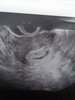

Ja robilam tylko usg. O plci z duzym prawdopodobieństwem ok 70/80% lekarz mowil juz w 13tc, pozniej tylko potwierdzal.Dziewczyny czy robiłyście badania genetyczne? W którym tygodniu dowiedziałyście się o płci?

Ja nie robiłam genetycznych. O płci dowiedziałam się już na pierwszych prenatalnych w 13tyg i cały czas się potwierdza